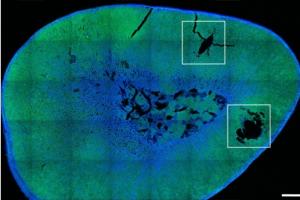

Actualité publiée le 06/10/2025IMAGERIE IRM : Du gadolinium dans les tissus humains ?